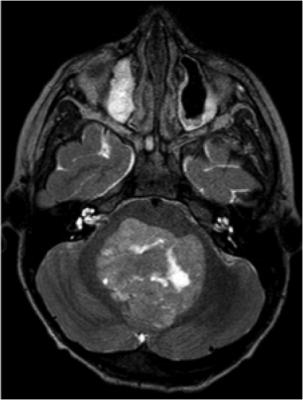

Failure of local control (LC), the primary endpoint of the study, was assessed through follow-up magnetic resonance imaging (MRI) by the study neuro-radiologist to determine whether local tumors recurred in the area treated with SRS. Researchers also examined the rates of overall survival (OS), development of distant brain metastases (DBM), time to WBRT and complications following SRS. Hazard ratios (HR) and corresponding confidence intervals (CI) were computed to compare treatment arms. The median follow-up time was 13 months, with a range of 0.3 to 71 months.

Radiosurgery to the surgical bed significantly reduced local recurrence of the resected tumor. At six months following treatment, LC rates were 83 percent for the SRS-cav group and 57 percent for the OBS group. At 12 months follow-up, the LC rates were 72 percent for the SRS-cav group, compared to 45 percent for the OBS group (HR, 0.46; p = 0.01).

Although SRS improved LC, there were no differences between treatment arms for regional recurrence, overall survival or time to WBRT. At 12 months after treatment, 58 percent of the SRS-cav patients had developed DBMs, compared to 67 percent in the OBS group, though the difference was statistically non-significant (HR, 0.79; p = 0.29). Median OS was 17 months for both groups (HR, 1.22; p = 0.37). WBRT was given to 24 of the 64 patients in the SRS-cav group within an average timeframe of 16.1 months, compared to 30 of 67 patients in the OBS group within an average timeframe of 15.2 months (HR, 0.8; p = 0.42). No significant complications were noted in the SRS-cav patients.